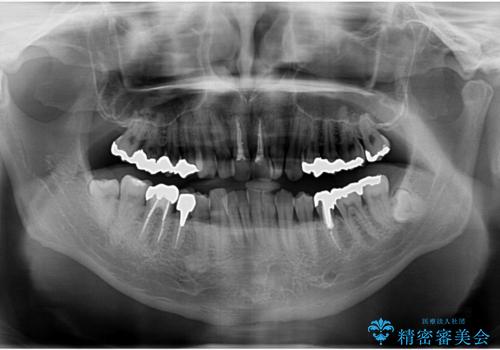

- 銀歯をすべてやり替えたいとのことで来院された患者様です。

再根管治療が必要なところは再根管治療から、そうでないところは補綴物のみをやり替えていくこととなりました。

銀歯のやり替えと並行してホワイトニングも行いました。

結果的には銀歯がすべて白くなり、前歯のガタつきもある程度改善され大変喜んでいただけました。

治療終了時からナイトガードを使用していただき、歯ぎしりによる破折を予防しています。